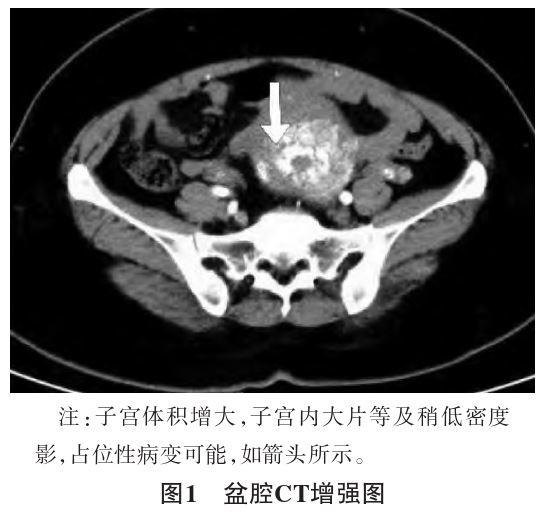

。盆腔CT平扫+增强示:子宫体积增大,子宫及双侧附件较多明显增粗迂曲杂乱血管影,双侧卵巢静脉增粗,右侧明显且右侧髂内静脉明显增粗迂曲,子宫内大片等及稍低密度影,占位性病变可能(见图1)。血β-hCG为239.17 U/L。患者系房间隔缺损封堵术后,存在MRI禁忌证,评估后未行MRI。患者入院后,请心内科会诊,会诊意见:停用阿司匹林,改用低分子肝素

2.3本例宫腔镜下诊断性刮宫术中急性失血性休克原因分析①解剖学异常:盆腔CT示子宫及双侧附件较多明显增粗迂曲杂乱血管影,双侧卵巢静脉增粗,右侧明显且右侧髂内静脉明显增粗迂曲。子宫动脉造影+双侧子宫动脉栓塞术中见子宫动脉迂曲增粗、分支多,血供丰富。在术中因手术操作导致血管损伤进一步导致大出血,且术前由于宫腔内占位性病变性质尚不明确,未在术前使用雌激素提高子宫肌层对宫缩剂的敏感性。②患者术前复查凝血相关项目无明显异常,但系房间隔缺损封堵术后,于心内科规律复查凝血功能调整抗凝药,该病史可能隐藏稽留流产相关的凝血功能障碍。③患者停经时间较长,胎儿及胎盘机化组织、残留组织与子宫壁肌层粘连或向肌层深层嵌入,组织与子宫肌层分界不清,组织粘连易损伤肌层及周围血管导致大出血。④诊断性刮宫术中退变的胎盘组织被破坏后大量释放凝血活酶进入母血循环,引起凝血功能障碍,造成术中出血增加。⑤胚胎死亡后,胎儿血管内皮细胞及上皮细胞损伤,释放大量的组织因子进入母体循环系统,引起凝血功能障碍[4]。⑥患者系多发性子宫肌瘤,肌瘤周围血管较丰富,可能导致子宫肌层侧支循环丰富,且肌瘤也可导致宫腔变形,导致宫腔镜手术操作困难及出血风险较大。该患者发生急性失血性休克时及时纠正休克、积极扩容、输血纠正贫血、宫腔球囊压迫止血、急诊行双侧子宫动脉栓塞治疗,挽救了患者生命,且为二次手术提供了较好的手术时机和条件,避免了切除子宫。